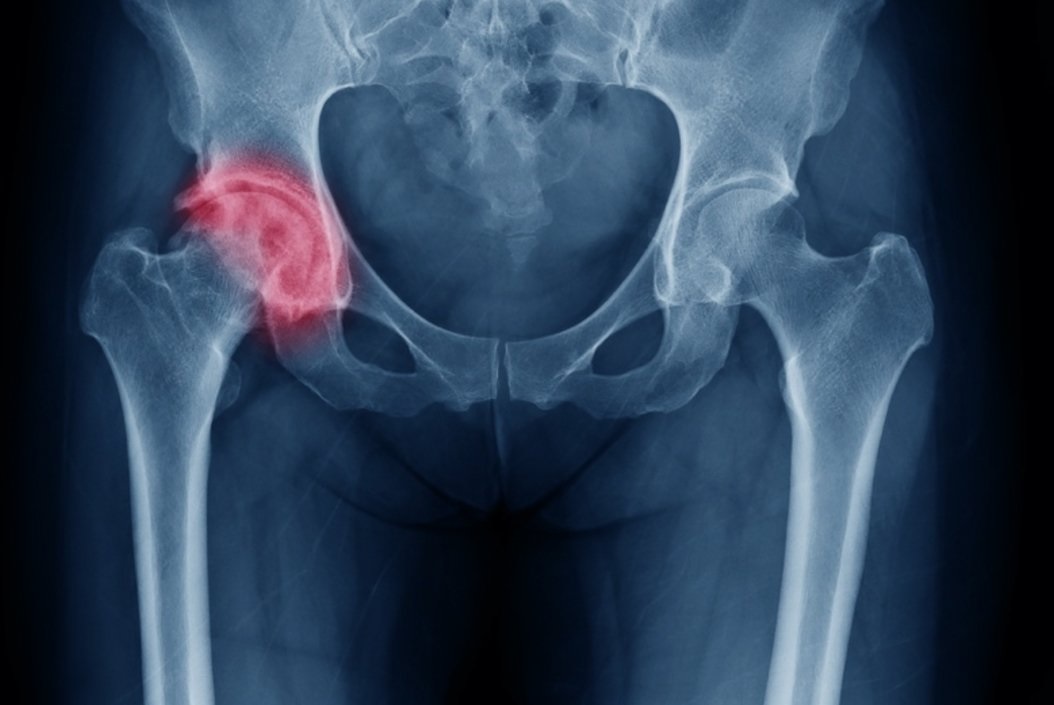

Τι είναι η οστεοαρθρίτιδα του ισχίου

Η οστεοαρθρίτιδα του ισχίου είναι μια πολύ συχνή πάθηση που χαρακτηρίζεται από πόνο στο ισχίο και στη βουβωνική χώρα και δυσκαμψία. Αποτελεί μια προοδευτική εκφυλιστική πάθηση που αφορά κυρίως ασθενείς μεγαλύτερης ηλικίας. Με την πάροδο του χρόνου ο χόνδρος μέσα στην άρθρωση του ισχίου γίνεται λεπτότερος και πιο εύθραυστος, με αποτέλεσμα οι οστικές επιφάνειες της άρθρωσης να έρχονται σε επαφή μεταξύ τους και να τρίβονται, προκαλώντας έτσι φλεγμονή με πόνο και δυσκαμψία. Ένα από τα κύρια συμπτώματα της οστεοαρθρίτιδας του ισχίου είναι ο έντονος πρωινός πόνος και η δυσκαμψία, που μειώνονται αργά με ήπια δραστηριότητα και κίνηση. Ο πόνος μπορεί να ακτινοβολεί στο γλουτό, στην εξωτερική επιφάνεια του μηρού και προς τα κάτω στο πόδι έως το γόνατο. Ο πόνος επιδεινώνεται με την φόρτιση, την ορθοστασία και την ανύψωση από καθιστή σε όρθια θέση.